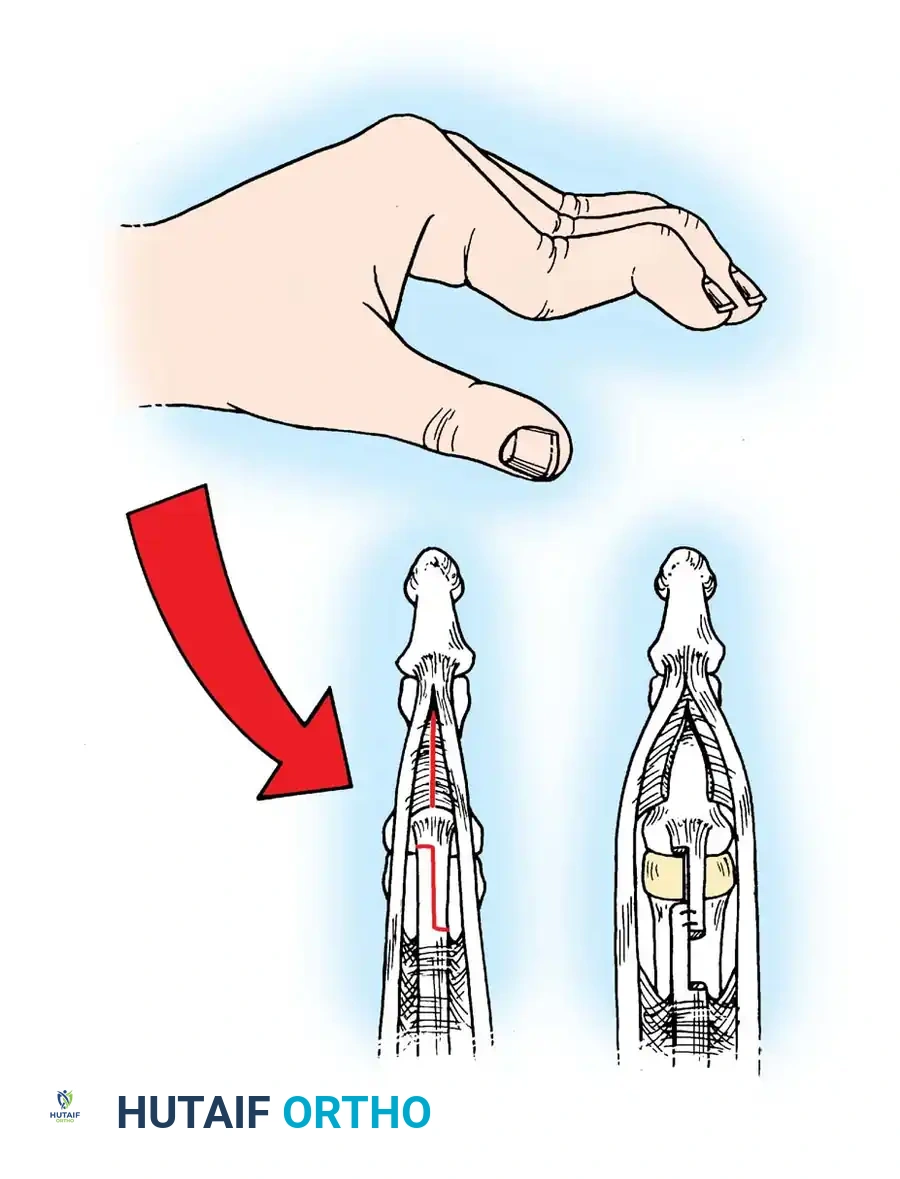

The intrinsic plus deformity is characterized by flexion of the metacarpophalangeal (MCP) joints and extension of the proximal interphalangeal (PIP) joints. It is caused by the tightness, spasm, and eventual ischemic contracture of the intrinsic muscles (lumbricals and interossei) secondary to rheumatoid inflammation.

In hands with a fixed intrinsic plus deformity, the PIP joint cannot be flexed while the MCP joint is fully extended. This deformity frequently develops in combination with volar subluxation of the MCP joints and ulnar deviation of the fingers.

The Bunnell Test for Intrinsic Tightness:

To perform this test, the MCP joint is passively held in maximum extension. This maneuver places the intrinsic muscles on stretch. If the intrinsics are tight, passive flexion of the PIP joint is prevented or significantly limited. Conversely, when the MCP joint is passively flexed (relaxing the intrinsics), passive flexion of the PIP joint increases.

Fig. 70-11 The Bunnell test for intrinsic tightness. Extension of the MCP joint exacerbates PIP extension forces if the intrinsics are contracted.

Surgical Warning: With ulnar drift of the fingers, intrinsic tightness may be present only on the ulnar side. To test this accurately, axial alignment of the finger with the metacarpal must be maintained. Any ulnar deviation at the MCP joint during the test slackens the intrinsics on the ulnar side and will yield a false-negative result.

A tight first volar interosseous muscle pulls the extended index finger ulnarward. If the finger is held in line with the second metacarpal during the test, tightness of this specific muscle can be isolated. The first volar interosseous is a flexor and adductor of the second MCP joint, whereas the first dorsal interosseous is typically an abductor only.